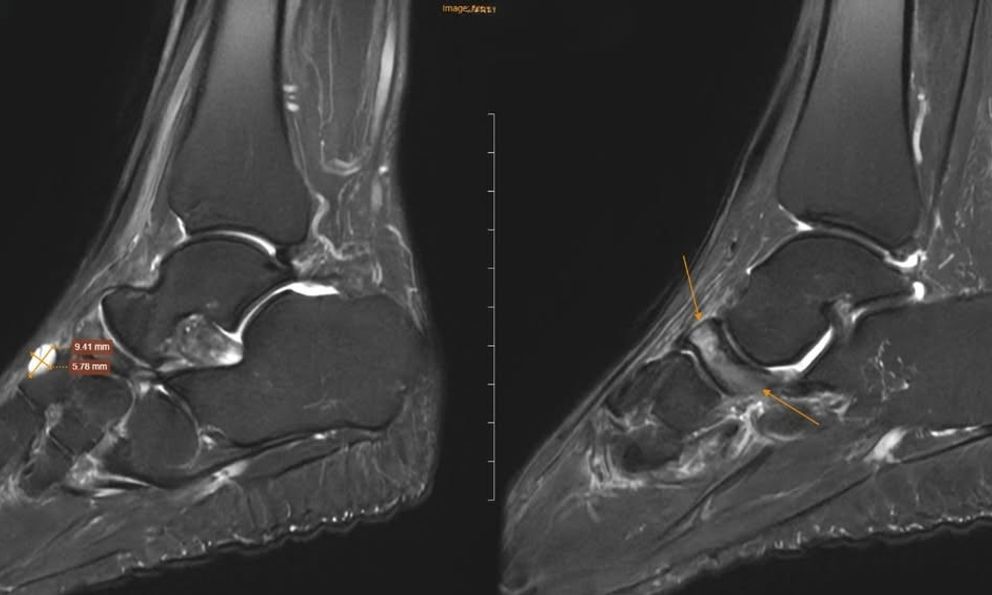

Để xác định nguyên nhân, các bác sĩ đã chỉ định chụp cộng hưởng từ (MRI). Kết quả cho thấy xương ghe bị xẹp và biến dạng điển hình hình “dấu phẩy”, kèm đặc xương dưới sụn và phù tủy xương rõ rệt. Ngoài ra, nhiều tổn thương phối hợp cũng được ghi nhận như gai xương, phù dây chằng, tràn dịch khớp cổ chân.

Dựa trên lâm sàng và hình ảnh học, bệnh nhân được chẩn đoán theo dõi Hội chứng Mueller-Weiss ở chân phải và phù tủy xương sên trái.